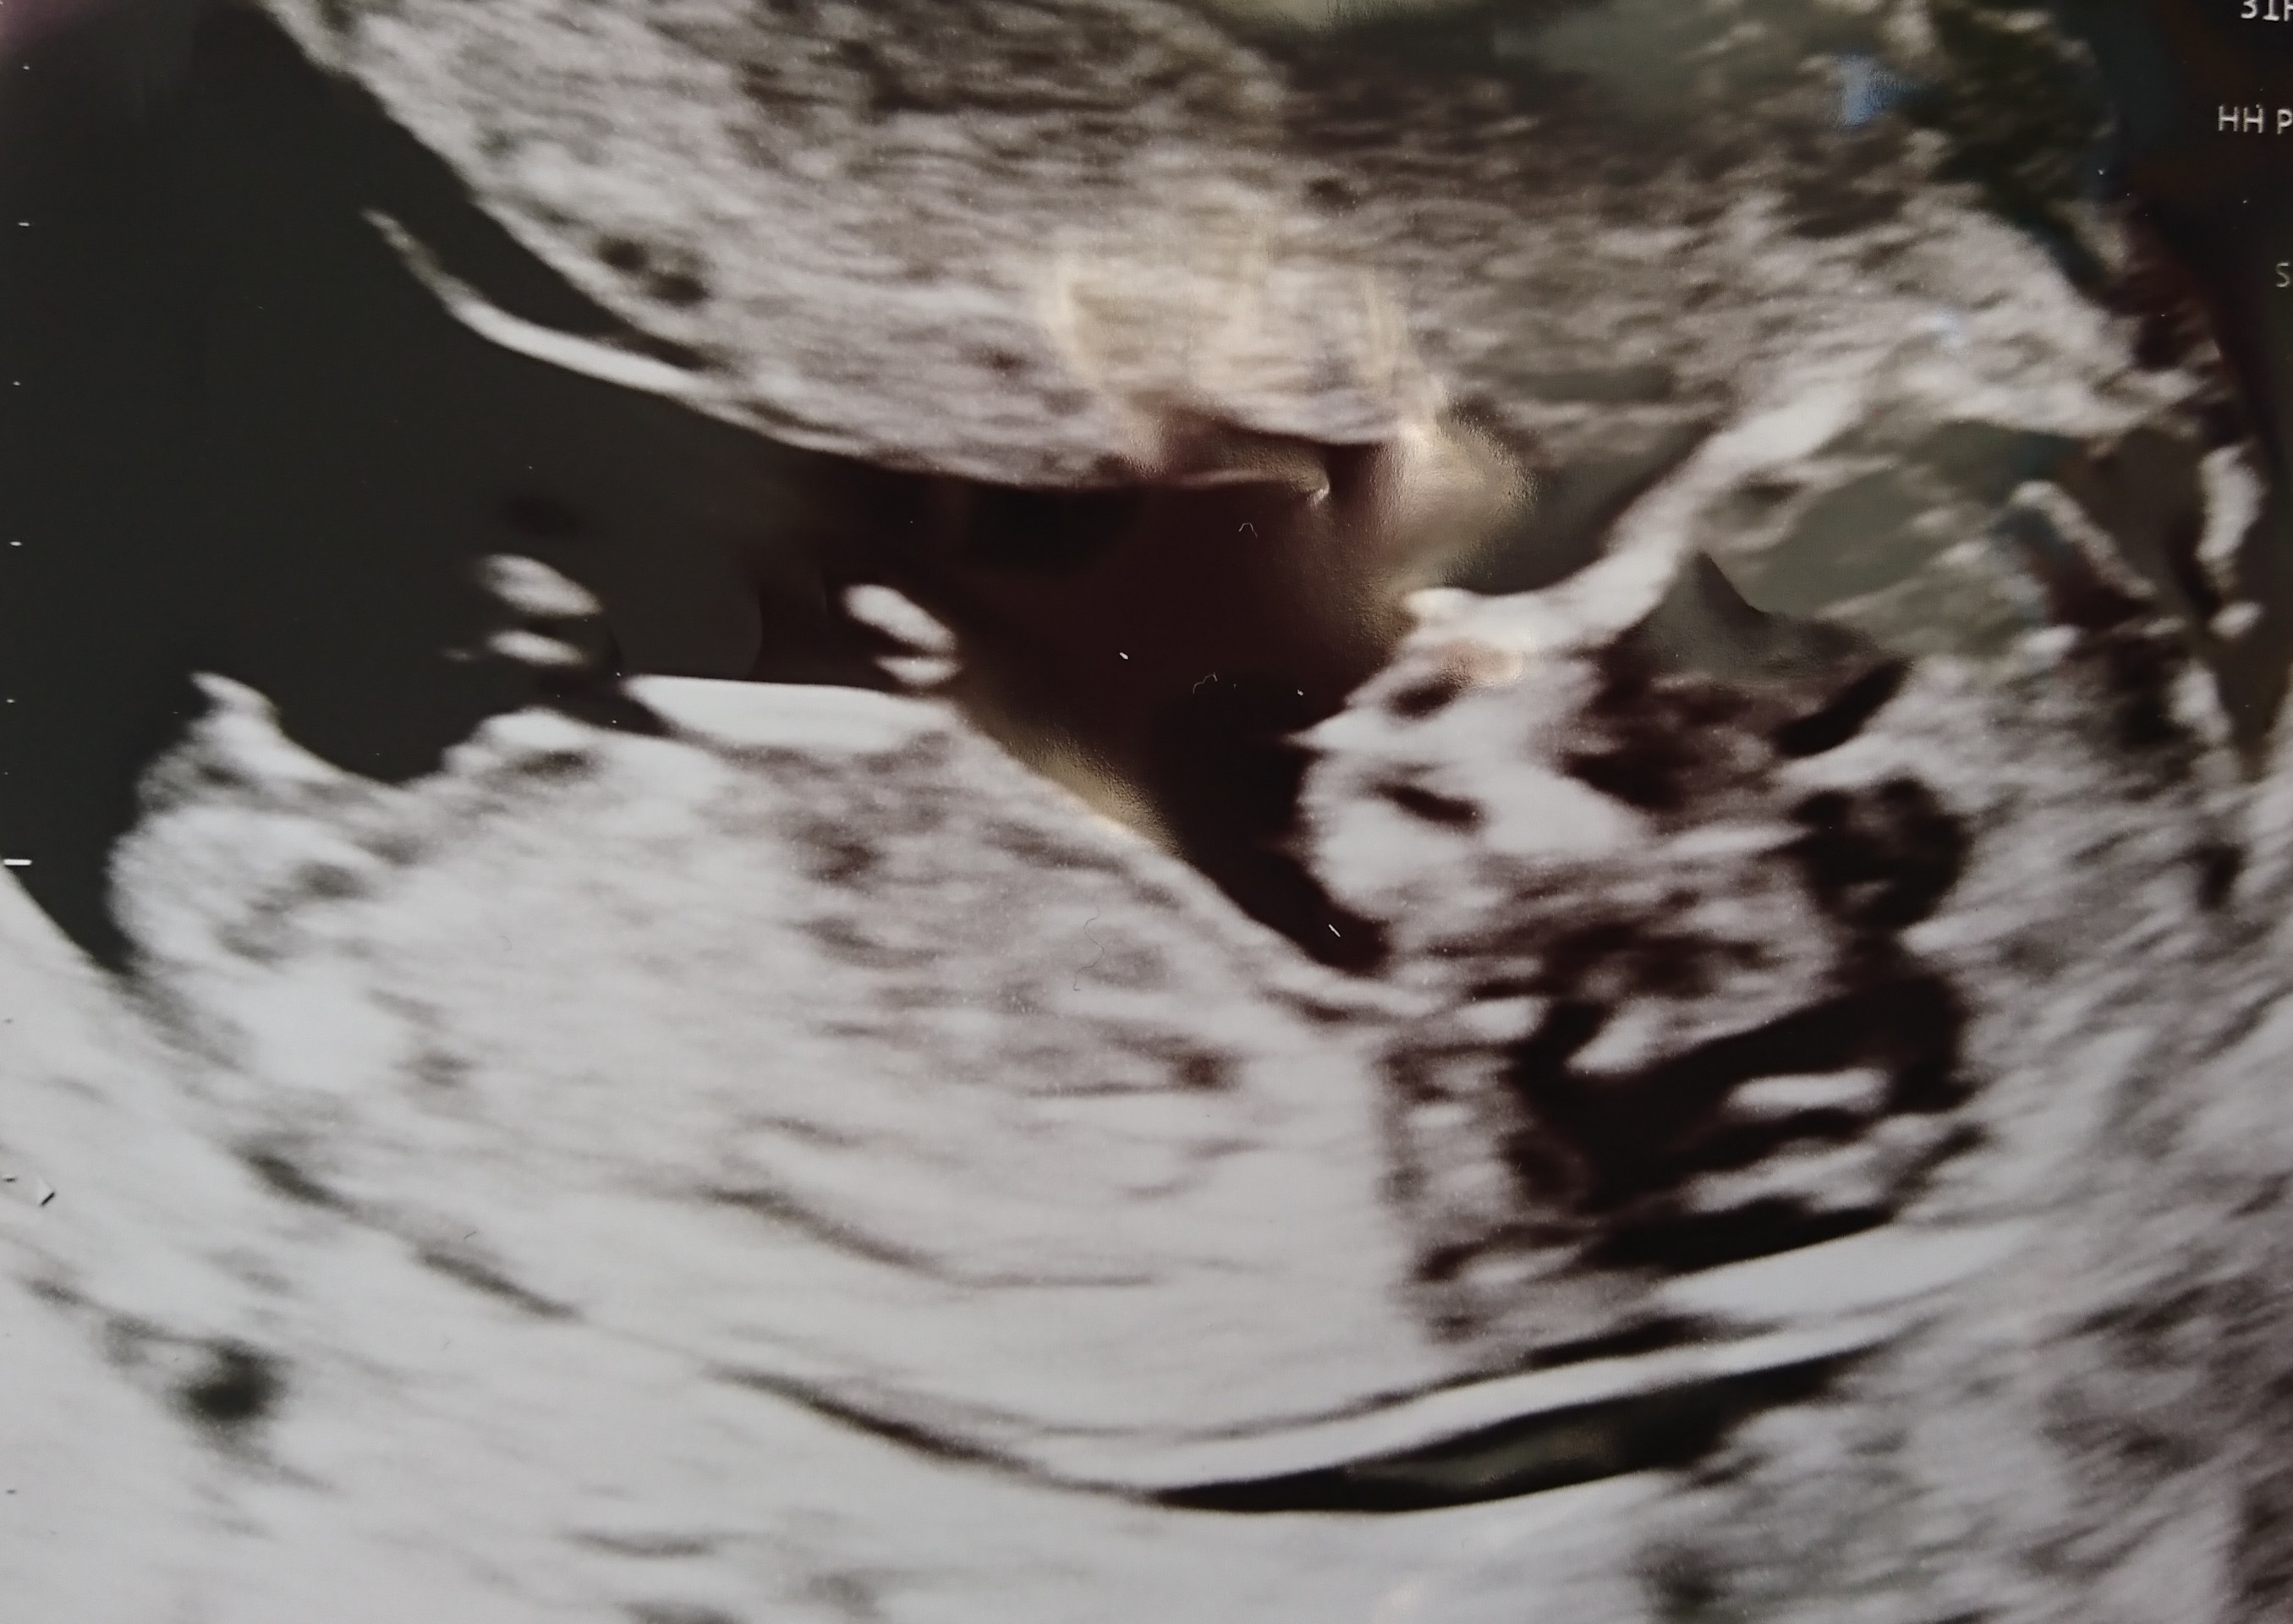

Hi Ladies. Here is pictures from my NT scan at 13 weeks.

I have been looking at many confirmed nub pictures. I am confused because it look boyish and girlish to me. It also did during my scan. At some point it looked boyish, but I saw a forknub that made me think girl. Do you think it looks like a boy or girl? :nails:

Attachment 41161Attachment 41160